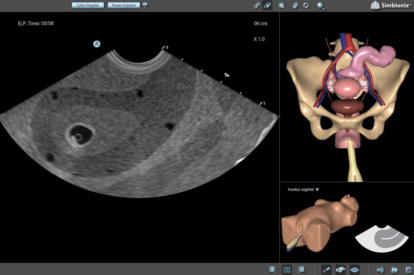

Ultrasound Mentor accelerates the development of basic to advanced technical and cognitive skills, by providing not only the probe manipulation training, but also a didactic environment enabling structured, self-guided learning including step-by-step instructions and educational aids such as 3D anatomical map and probe positioning assistant, all backed up with our progress monitoring tool MentorLearn.

Basic GYN Module

OB 1st Trimester Module